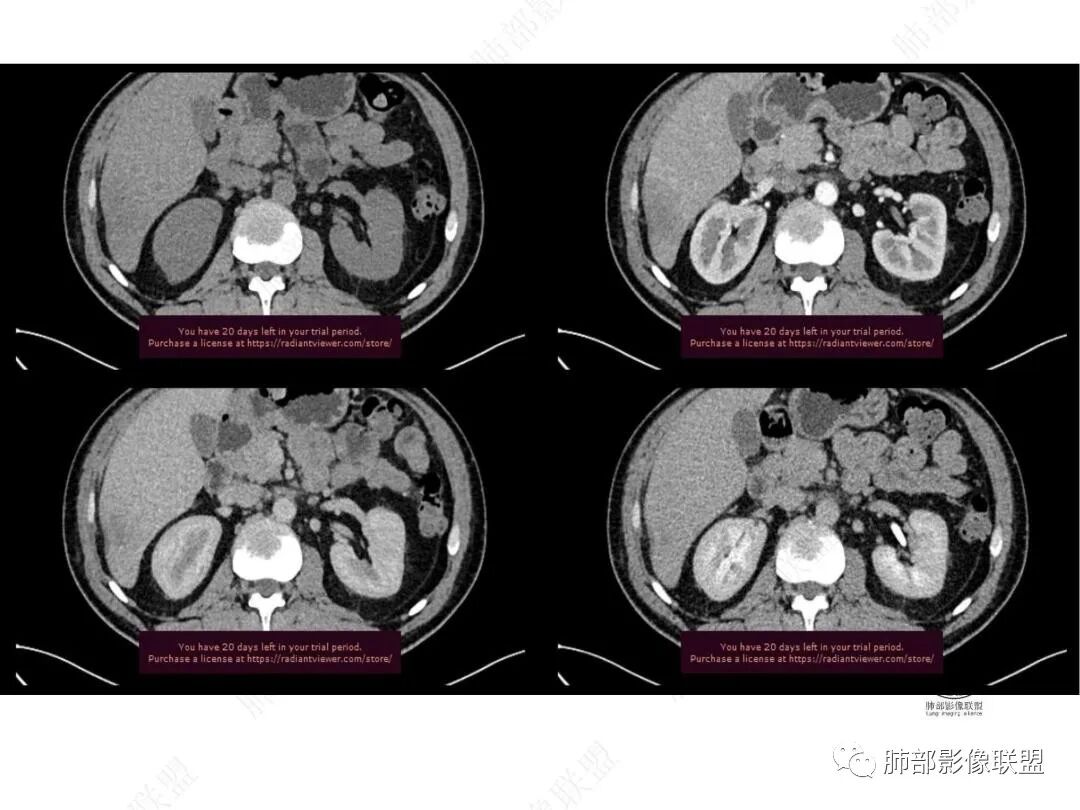

增强图像

4.肝脏病灶没有假包膜,没有动脉早期强化,没有肝硬化,未见扩张胆管,未见环形强化,也未显示靶征,缺乏肝细胞肝癌、胆管细胞癌、转移癌或肝脓肿特征。

但回顾性分析,如此少血供确实可以符合淋巴瘤,如果密度更均匀一点的话,这是我们有所忽略的地方。

肝脏病变明确,是轻度强化,延迟强化特点,边缘模糊,有轻微的包膜挛缩。